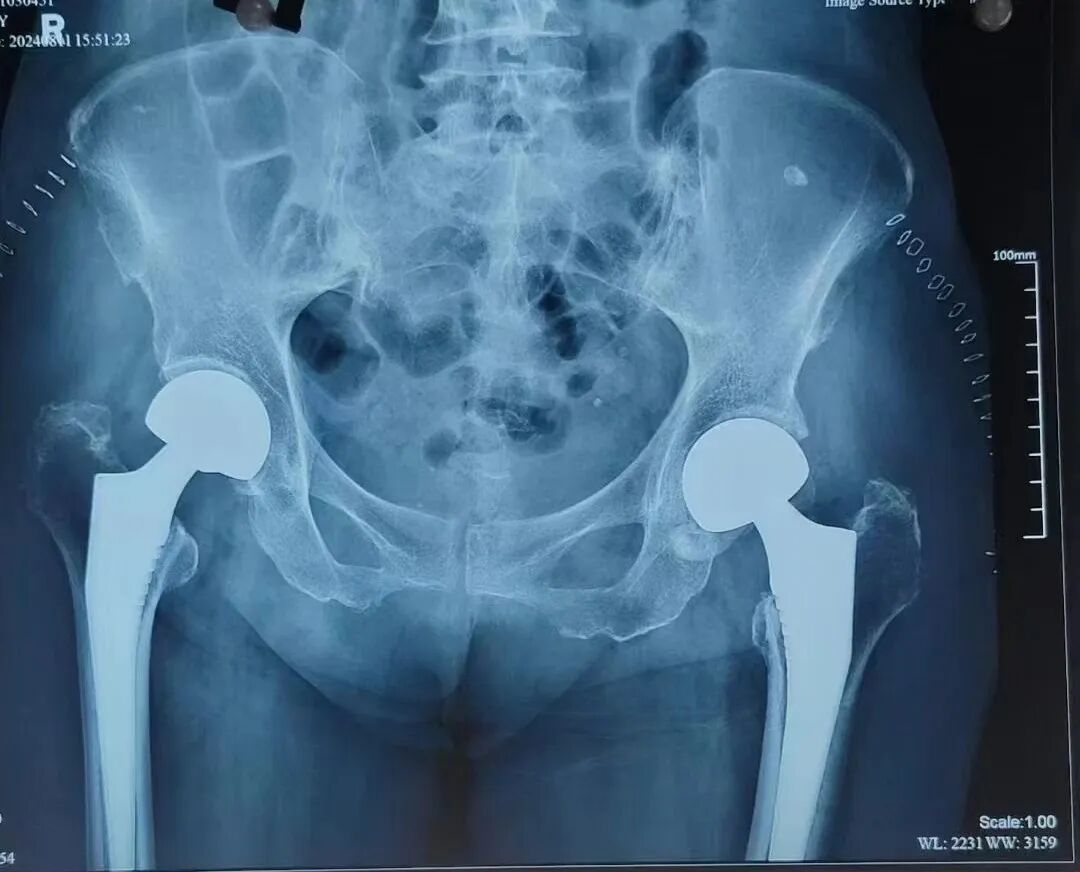

家住西影路的唐老太(化名)今年83岁,一个月内先后不慎摔倒了两次,结果导致左右两侧股骨颈均骨折,这使得她无法下地行走,就连翻身都极为困难。在家人陪同下来到陕西冶金医院骨科就诊。

考虑到老人年龄较大且左右两侧股骨颈均骨折,为避免二次手术带来的多重创伤,骨科主任赵学刚决定一次手术解决两侧问题。同期行双侧人工股骨头置换术,成功为她替换了双侧髋关节,手术过程十分顺利。术后第三天就能下地功能锻炼。老人和家属非常满意,对骨科医护人员精湛技术及悉心护理更是高度认可。出院后,特地为骨科送来了锦旗,以此表达诚挚谢意。